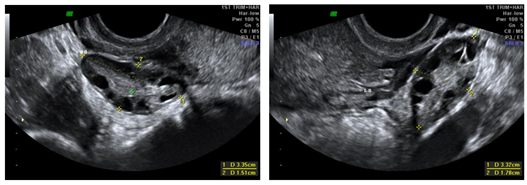

We report a rare case of intramyometrial ectopic pregnancy in a 27year old lady, P3L3 who presented to the emergency department at 8 weeks of gestation with complaints of pelvic pain and haemorrhage not subsiding with medical management. Transvaginal ultrasound revealed an exocentric gestational sac with thick decidua reaction and a “Ring of fire” appearance on color Doppler. Uterine cavity was empty and no adnexal masses visualized. Furthermore, MRI of the pelvis with contrast was done to confirm the location of the ectopic gestation which revealed a well defined T1 isointense T2 hyperintense lesion in the anterior myometrium abutting the junctional zone and showing contrast enhancement. Endometrial stripe was seen separately with an empty uterine cavity. Pouch of Douglas had no free fluid. On diagnostic laparoscopy, an asymmetrically enlarged swollen anterior wall of the uterus was seen. Hysteroscopy was performed concurrently demonstrating an empty uterine cavity. Medical management with methotrexate was initiated following confirmation of the diagnosis. Beta HCG at the time of diagnosis was 9949mIU/ml. She was followed up until the hormone levels returned to baseline and serial scans showed a healed solid collection (Figures 1‒7).

Figure 5 & 6 Transvaginal ultrasound images showing Right and Left ovaries with no adnexal lesions.